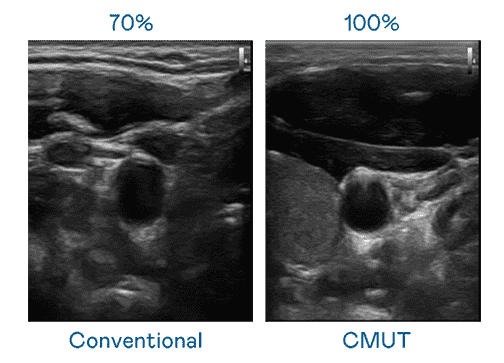

CMUT 技术是一种用电容式微机电元件来产生超音波讯号的技术。。与传统 PZT 压电式技术相比,,,CMUT 频宽增加 30%,,更宽频的超音波讯号让影像解析度大幅提升,,,是实现高影像品质医疗超音波扫描、、、、促进精准医疗发展的关键技术。。。

超音波影像的解析度高低,,,,首先取决于探头能发出的讯号频宽。。。。财神娱乐 CMUT 可提供高清晰的超音波讯号,,提供高频宽、、高灵敏度、、、、影像纹理细节更高的超音波影像,,协助医护人员缩短影像判读时间及利用精准的医疗影像进行诊断。。。